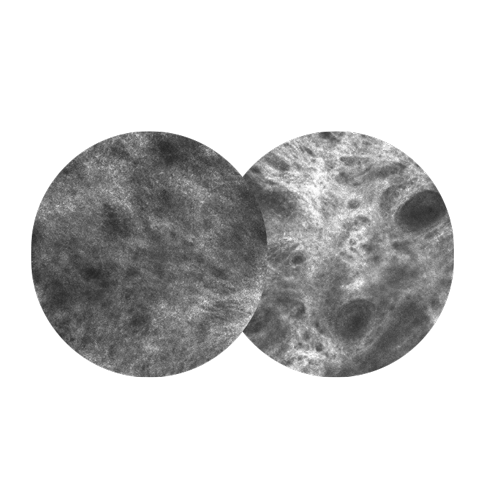

The VivaScope 1500 offers physicians, clinicians as well as medical and cosmetic researchers the possibility to non-invasively examine skin In Vivo, at cellular resolution and in real time.The VivaScope 1500 provides a non-invasive view into the epidermis all the way down to the superficial dermis. A near-infrared laser (830 nm) penetrates the superficial layers and is reflected by components of the skin.

Excellent comparability of images to examine treatment over time beneath the skin. In addition, it’s is perfect for cosmetic and medical research.

The VivaScope 1500 is perfect for melanocitic and non-melanocitic lesions on the body. For your every day routine.